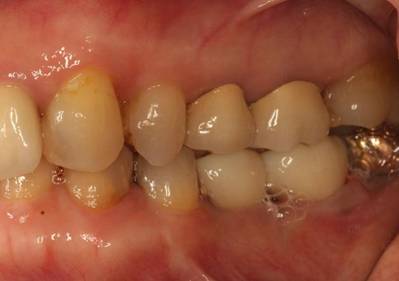

歯周病で抜歯せざるを得ず、インプラントを希望されたケース(使用インプラントはスプライン)

術前。すべての歯が歯周病の末期状態でブリッジ全体がうごいて噛めないとの訴え。右上の犬歯が腫れていました

固定式のブリッジが入っていましたが歯周病で動いています

下顎前歯部には歯石の沈着がみられます